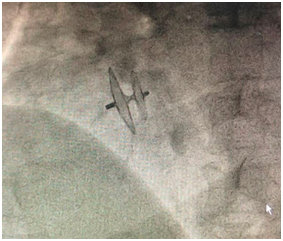

1月30日,金泽宁为患者进行卵圆孔未闭封堵手术,手术持续大约40分钟,患者术后恢复良好,当晚即可正常下地活动。